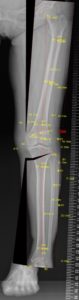

3. Double level osteotomy(DLO)